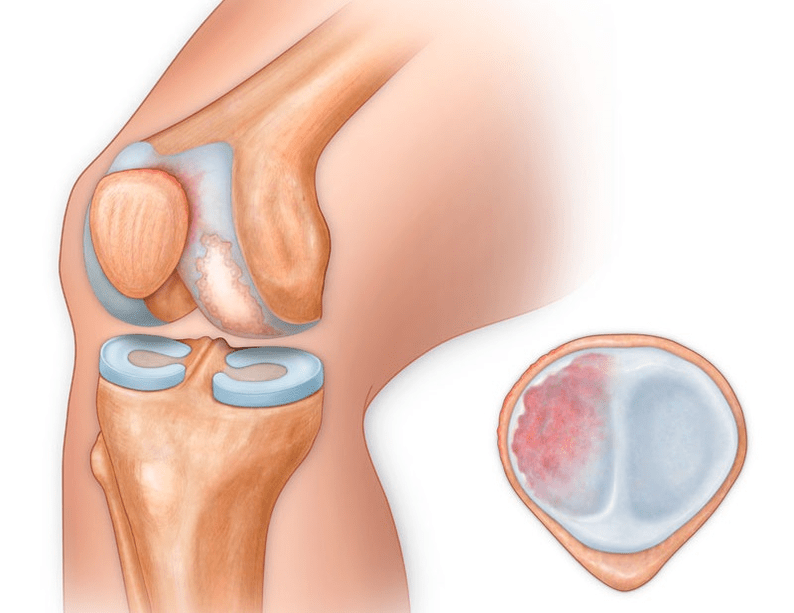

Arthrosis of the knee joint (gonarthrosis)is a progressive chronic disease of the knee joint, accompanied by damage, thinning and destruction of its cartilaginous part (the articular surfaces of the femur and tibia), as well as damage to the subchondral bone.Research (arthroscopy and MRI) has proven that the meniscus and synovial membrane are also involved in the process, along with damage to the articular cartilage.Gonarthrosis is one of the most common orthopedic pathologies.It has synonyms - osteoarthritis (OA), deforming arthrosis.The disease is an important socio-economic problem, because it is widespread and significantly worsens the quality of life of patients due to constant pain and, in addition, causes high disability.

Until the mid-eighties of the last century, there was no unified definition of the disease.Only until 1995, the osteoarthritis committee of the American College of Rheumatology characterized the disease as the result of mechanical and biological factors that lead to an imbalance between the processes of degradation and synthesis of the extracellular matrix of articular cartilage.As a result, fibers break down and degenerate, cracks, osteosclerosis and compaction appear in the cortical layer of subchondral bone, osteophytes grow, and subchondral cysts form.

With arthrosis (osteoarthrosis), along with progressive destruction of cartilage, loss of elasticity and shock absorption properties, bones are gradually involved in the process.Under load, sharp edges (exostoses) appear, which are mistakenly considered "salt deposits" - salt deposition does not occur with classic arthrosis.As arthrosis progresses, it continues to "eat" the cartilage.Then the bone is deformed, cysts are formed there, all the structures of the joint are affected, the leg bends.

In addition to the inner or outer part of the knee, arthrosis can also affect the surfaces between the patella and the intercondylar groove of the femur.This is called selectionpatellofemoral arthrosis.